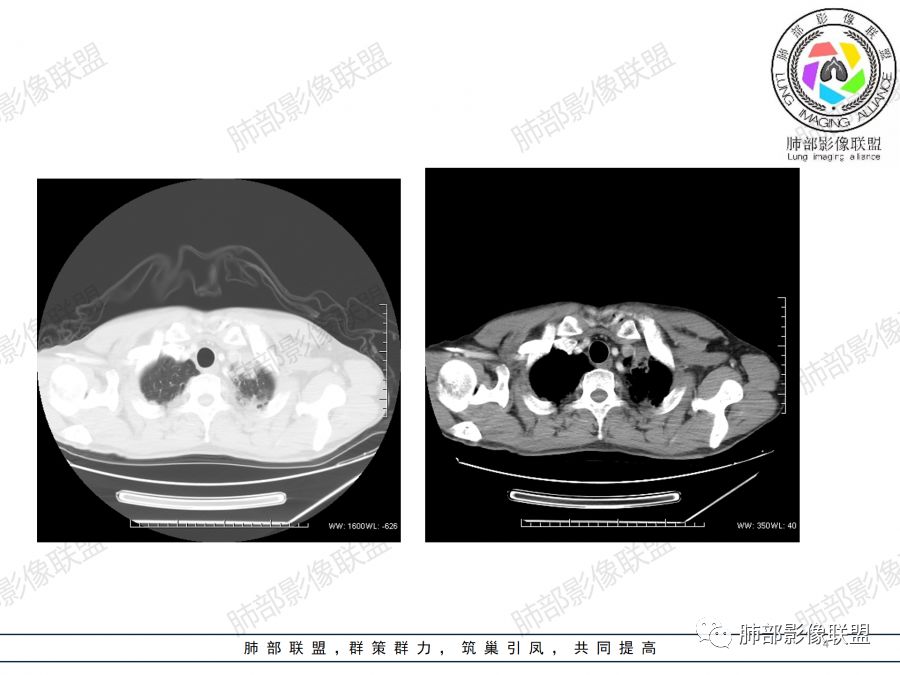

患者中年男性,咳嗽、咳痰1月余入院。胸部CT:左肺上叶尖段近胸膜下肿块占位灶,边缘光滑,边界清楚,周围可见片状磨玻璃影,可见平直、毛刺、分叶征象,增强轻度强化,内可见点片多发低密度区及部分血管影,与支气管关系欠清,左肺上叶背侧胸膜增厚、胸膜下结节,右肺似见多发小结节灶,淋巴结不大。综合考虑良性病变,结核可能性大,鉴别腺癌并肺内、胸膜转移及淋巴瘤等。

男,47岁,咳嗽咳痰一月。病灶位于左内乳动脉内缘,定位肺内,呈团片状异常密度影,整体沿支气管气管束走形分布,由肺门达胸膜下,于近肺门侧病灶形态相对较小,病灶远端相对较大,病灶整体密度偏均匀,强化偏明显,病灶内见多发支气管扩张并粘液栓形成,且扩张支气管粗细不均,直达病灶以远,病灶内血管走形正常、粗细均匀,病灶周围见边缘模糊磨玻璃及少许腺泡结节。左肺门及纵隔略大淋巴结,左侧胸膜局限性增厚。诊断:左肺上叶前段异常密度影,炎性肉芽肿性病变可能,结核不能除外,建议穿刺活检除外恶性肿瘤。

2.双上肺多发病灶,左肺上叶病灶沿血管支气管束分布,由外朝内,以平直收缩为主,周围有斑片渗出,胸膜糊墙,支持炎性病灶或是伴有肿瘤灶可能性。

两上肺发病,多支持结核等感染,但结核基础上伴发肺癌并不鲜见!